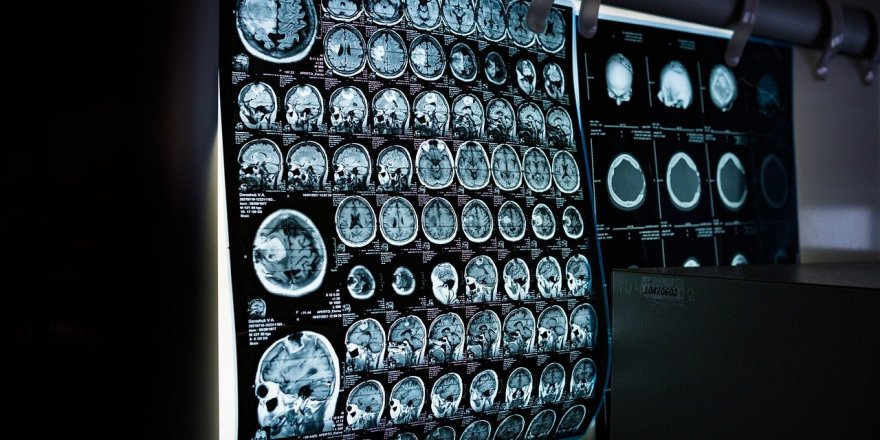

Bilim insanları, ölmekte olan bir insanın beyninin aktivitelerini ilk kez kayıt altına aldı.

"Rt.com"un haberine göre, bilim insanları, 87 yaşındaki bir epilepsi hastasının kalp krizi geçirmesinin ardından ölümünün gerçekleştiği sırada kayıtta olan Elektroensefalografi (EEG) sayesinde beyin hareketliliğini inceledi.

87 yaşında hayatını kaybeden kişinin beyin aktivitelerinin 15 dakika boyunca devam ettiği ortaya konulurken, bu gelişmenin ölüm anında neler yaşandığına dair perde araladığı kaydedildi.